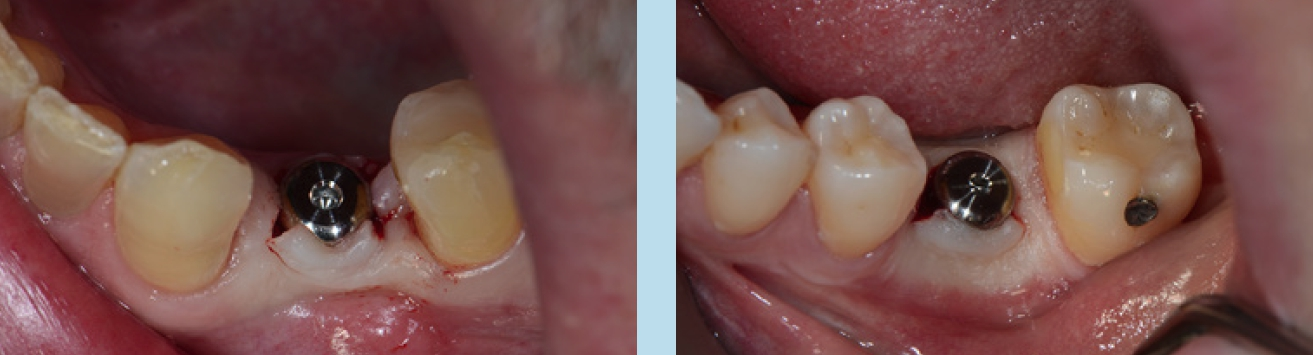

Je nach Implantathersteller stehen Gingivaformer mit unterschiedlichen Durchmessern für ein und denselben Implantatdurchmesser zur Verfügung. In der täglichen Praxis wird zu selten von dieser Möglichkeit Gebrauch gemacht, die Diskrepanz zwischen dem schmalen Diameter der Implantatschulter und dem breiteren physiologischen Durchtrittsprofil einer Molarenkrone bereits bei der Freilegung zu überbrücken.

Das Einzelimplantat anstelle einer konventionellen Brücke hat sich bewährt, da so weiterer Substanzverlust an Nachbarzähnen vermieden werden kann. Die prothetischen Komponenten bestehen bei vielen Systemen aus einem verschraubbaren Abutment und einer zementierten Krone oder aus einer direkt verschraubten Abutment-Kroneneinheit.